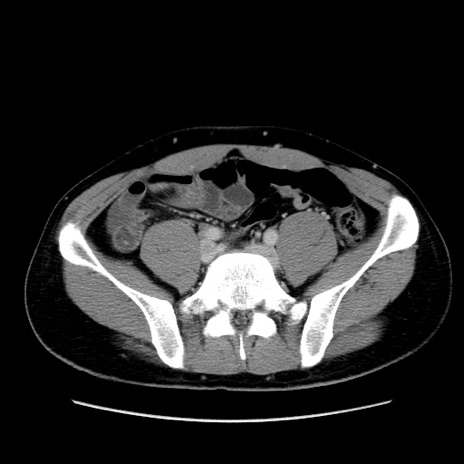

症例36(横断像)

【症例】20歳代 男性

【主訴】心窩部痛

【現病歴】今朝より上腹部痛あり。一旦軽快していたが再度出現したため救急要請。昨日夕に白身の魚を含む刺身を食べた。

【身体所見】BP 136/89mmHg、HR 74/min、BT 37.0℃、腹部:膨満、軟、心窩部に圧痛あり。反跳痛なし、筋性防御なし、腸雑音やや亢進あり。

【データ】WBC 17700、CRP 0.48